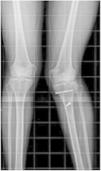

Por el bloqueo que presentaba la paciente en la rodilla se solicitó resonancia magnética en la rodilla afecta, que no reportó lesión ni en meniscos ni en ligamentos (fig. 2). Se complementa con estudios de imagen por la discrepancia en la longitud de las extremidades inferiores, que aparentemente es de 2cm, por lo que se solicitó telemetría radiográfica de miembros inferiores para determinar la discrepancia exacta (fig. 3).

Paciente masculino 17años de edad que refiere que hace 4años, mientras realizaba actividad deportiva (fútbol), sufrió traumatismo sobre su rodilla izquierda, presentando fractura a nivel de la meseta tibial, por lo que le realizaron osteosíntesis con tornillos. Actualmente consulta por deformidad en valgo de la rodilla izquierda, acortamiento y rotación interna de la extremidad durante la marcha. Se realizan estudios radiográficos para valorar el estado de partes óseas (fig. 4); así mismo, se solicita telemetría de miembros inferiores para valorar el acortamiento de la extremidad afecta (fig. 5).

La valoración de un paciente que presente deformidad en valgo de rodillas debe hacerse tanto clínica como radiológicamente. Radiológicamente deben realizarse mediciones de diferentes ángulos, pero el más importante es el ángulo femorotibial medido en la radiografía AP, ya que este ángulo es el que se suele tener en cuenta para decidir la conducta terapéutica que se va a seguir; valores superiores a los citados se consideran anormales. Es importante, además, realizar una medición clínica de ambos miembros para determinar si existe discrepancia de longitud. En caso de existir, esta debe corroborarse mediante la realización de telemetría radiológica de miembros inferiores, el cual nos informará más exactamente de la longitud de cada miembro.